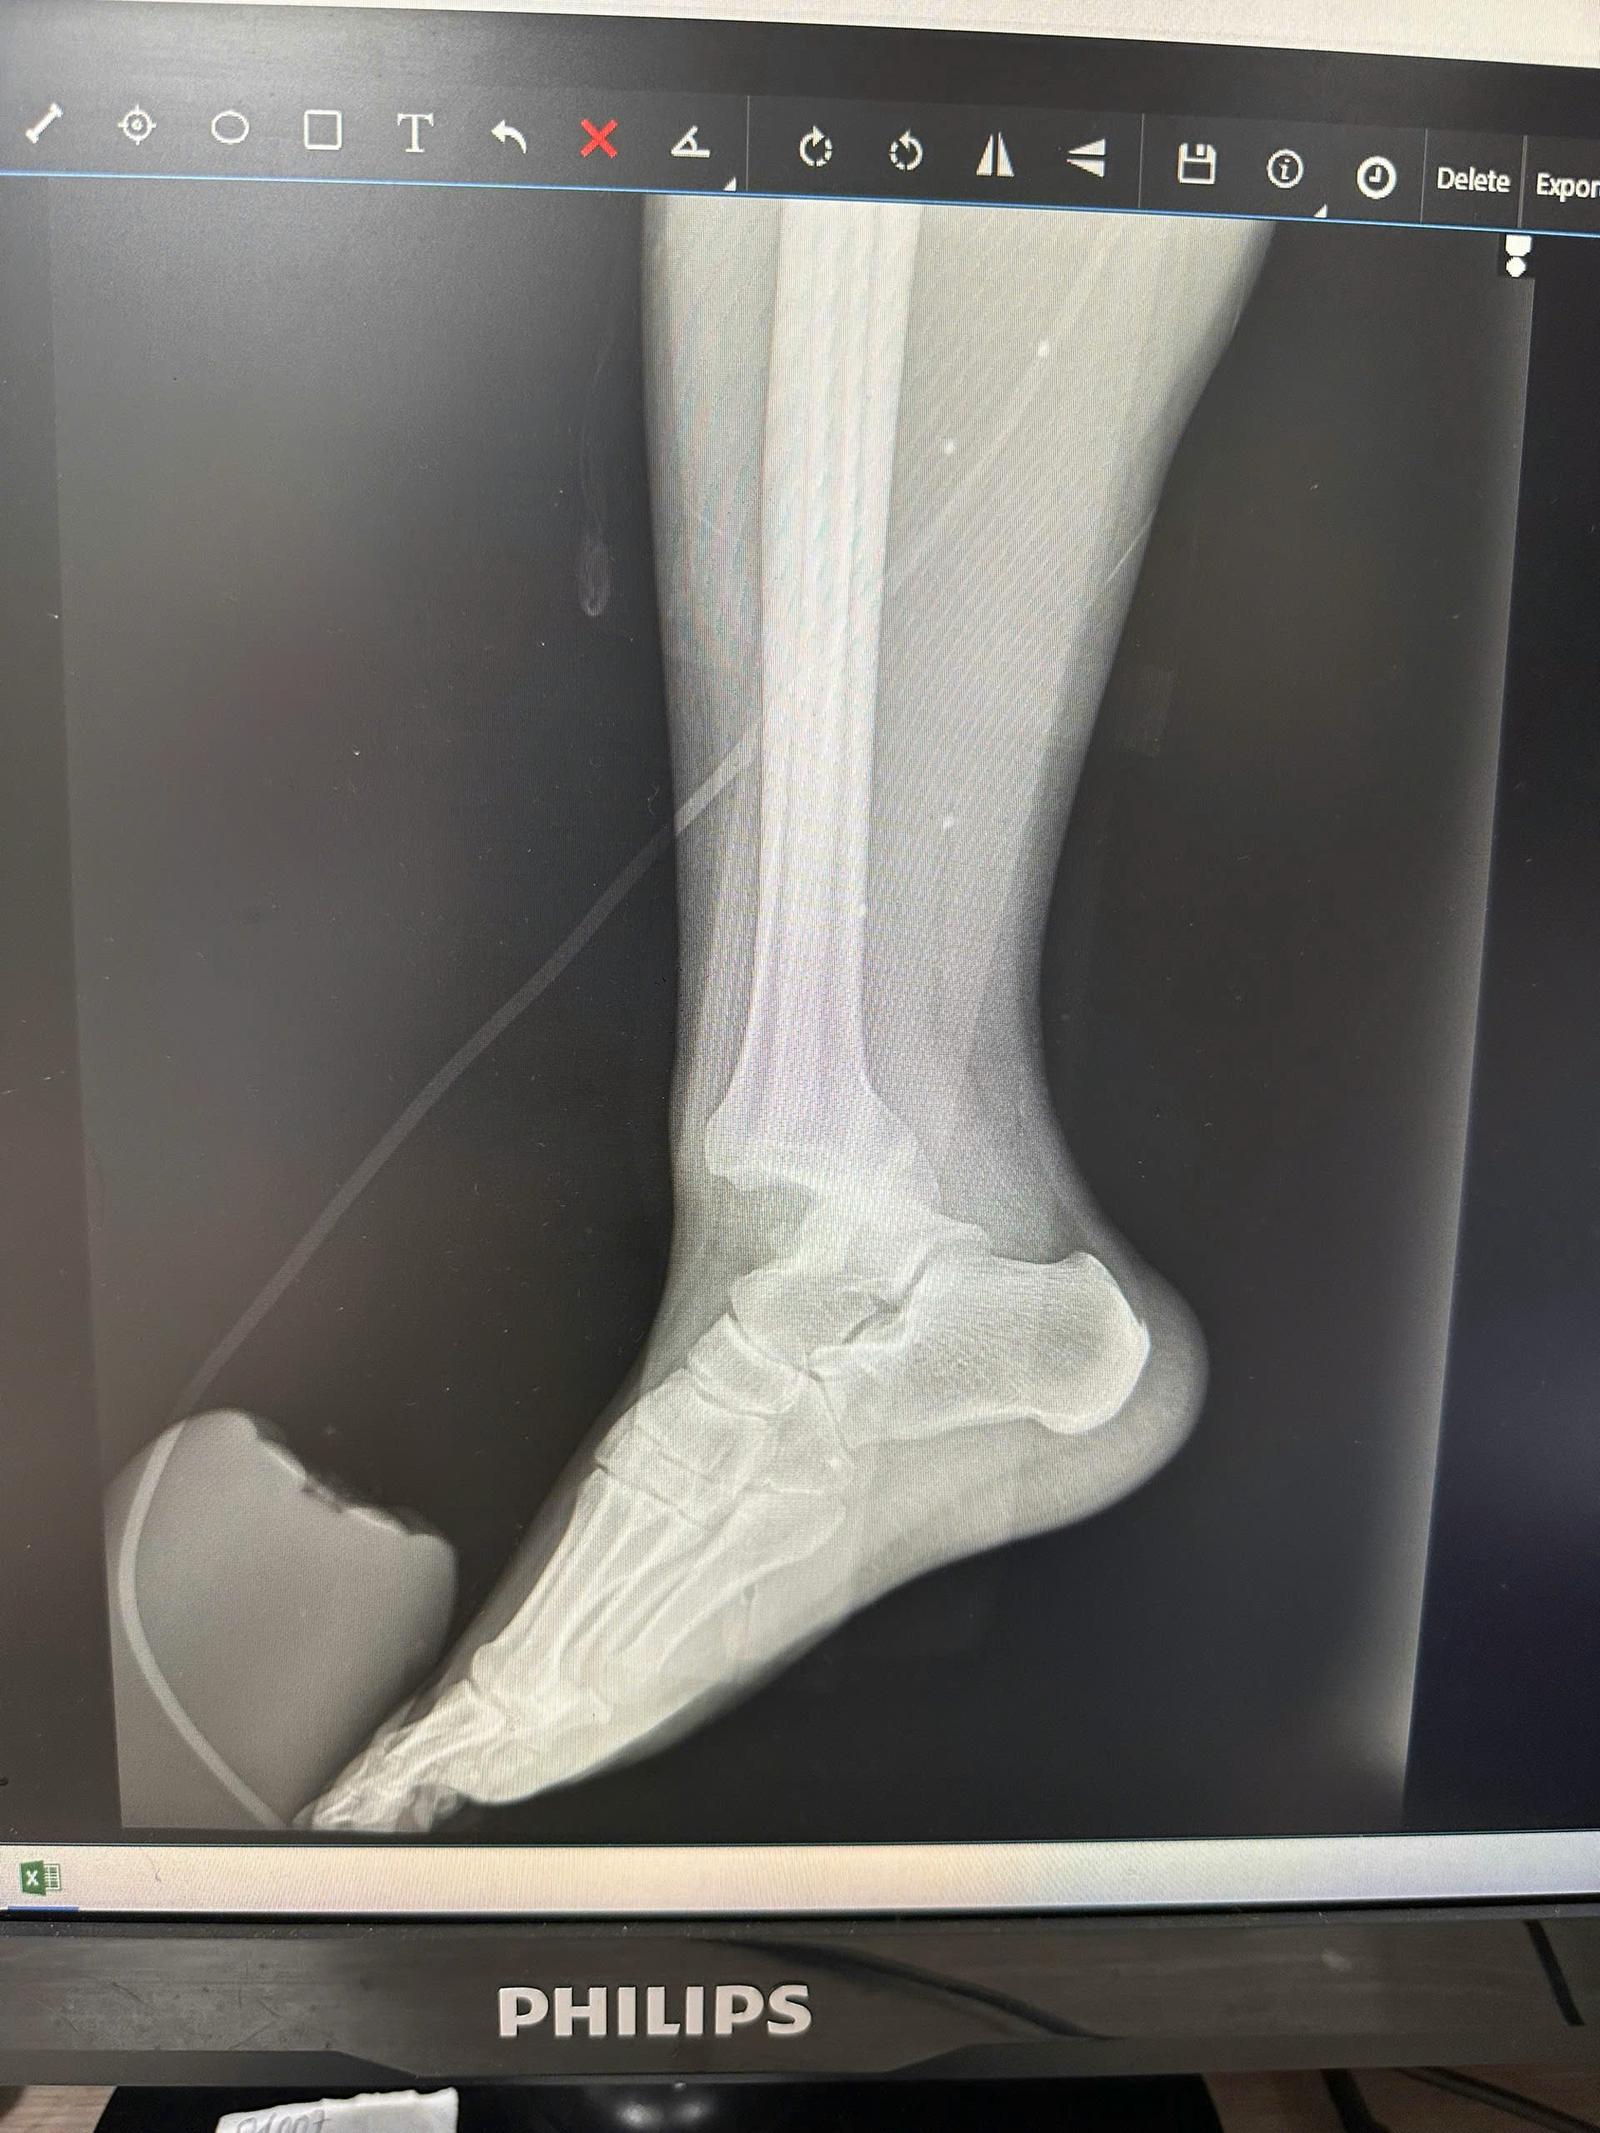

Đáng chú ý khi di chuyển đến Ngã Tư Nguyễn Chánh - Tú Mỡ, anh K. di chuyển hướng rẽ vào đường Tú Mỡ thì bất ngờ xe ô tô vượt lên tạt đầu và đâm vào xe máy, khiến cả xe và người anh K. bị đỗ xuống đường. Không dừng lại ở đó, sau khi đâm lần đầu, tài xế ô tô tiếp tục nhấn ga, đè lên xe máy và chân của nạn nhân, gây ra những chấn thương nghiêm trọng. May mắn, dù đã bị gãy chân nhưng anh K. vẫn kịp thời né tránh để không bị bánh xe ô tô chèn qua người.

Hình ảnh chụp X-quang chân nạn nhân

Dù người dân đã gọi công an, nhưng phải 30 phút sau lực lượng chức năng mới có mặt. Anh K. được đưa đi cấp cứu tại bệnh viện và được chẩn đoán gãy xương mác, xương chày, phải phẫu thuật. Đến thời điểm hiện tại, sau nhiều ngày xảy ra vụ việc, anh K. cho biết vẫn chưa nhận được sự giải quyết thỏa đáng từ phía cơ quan chức năng.